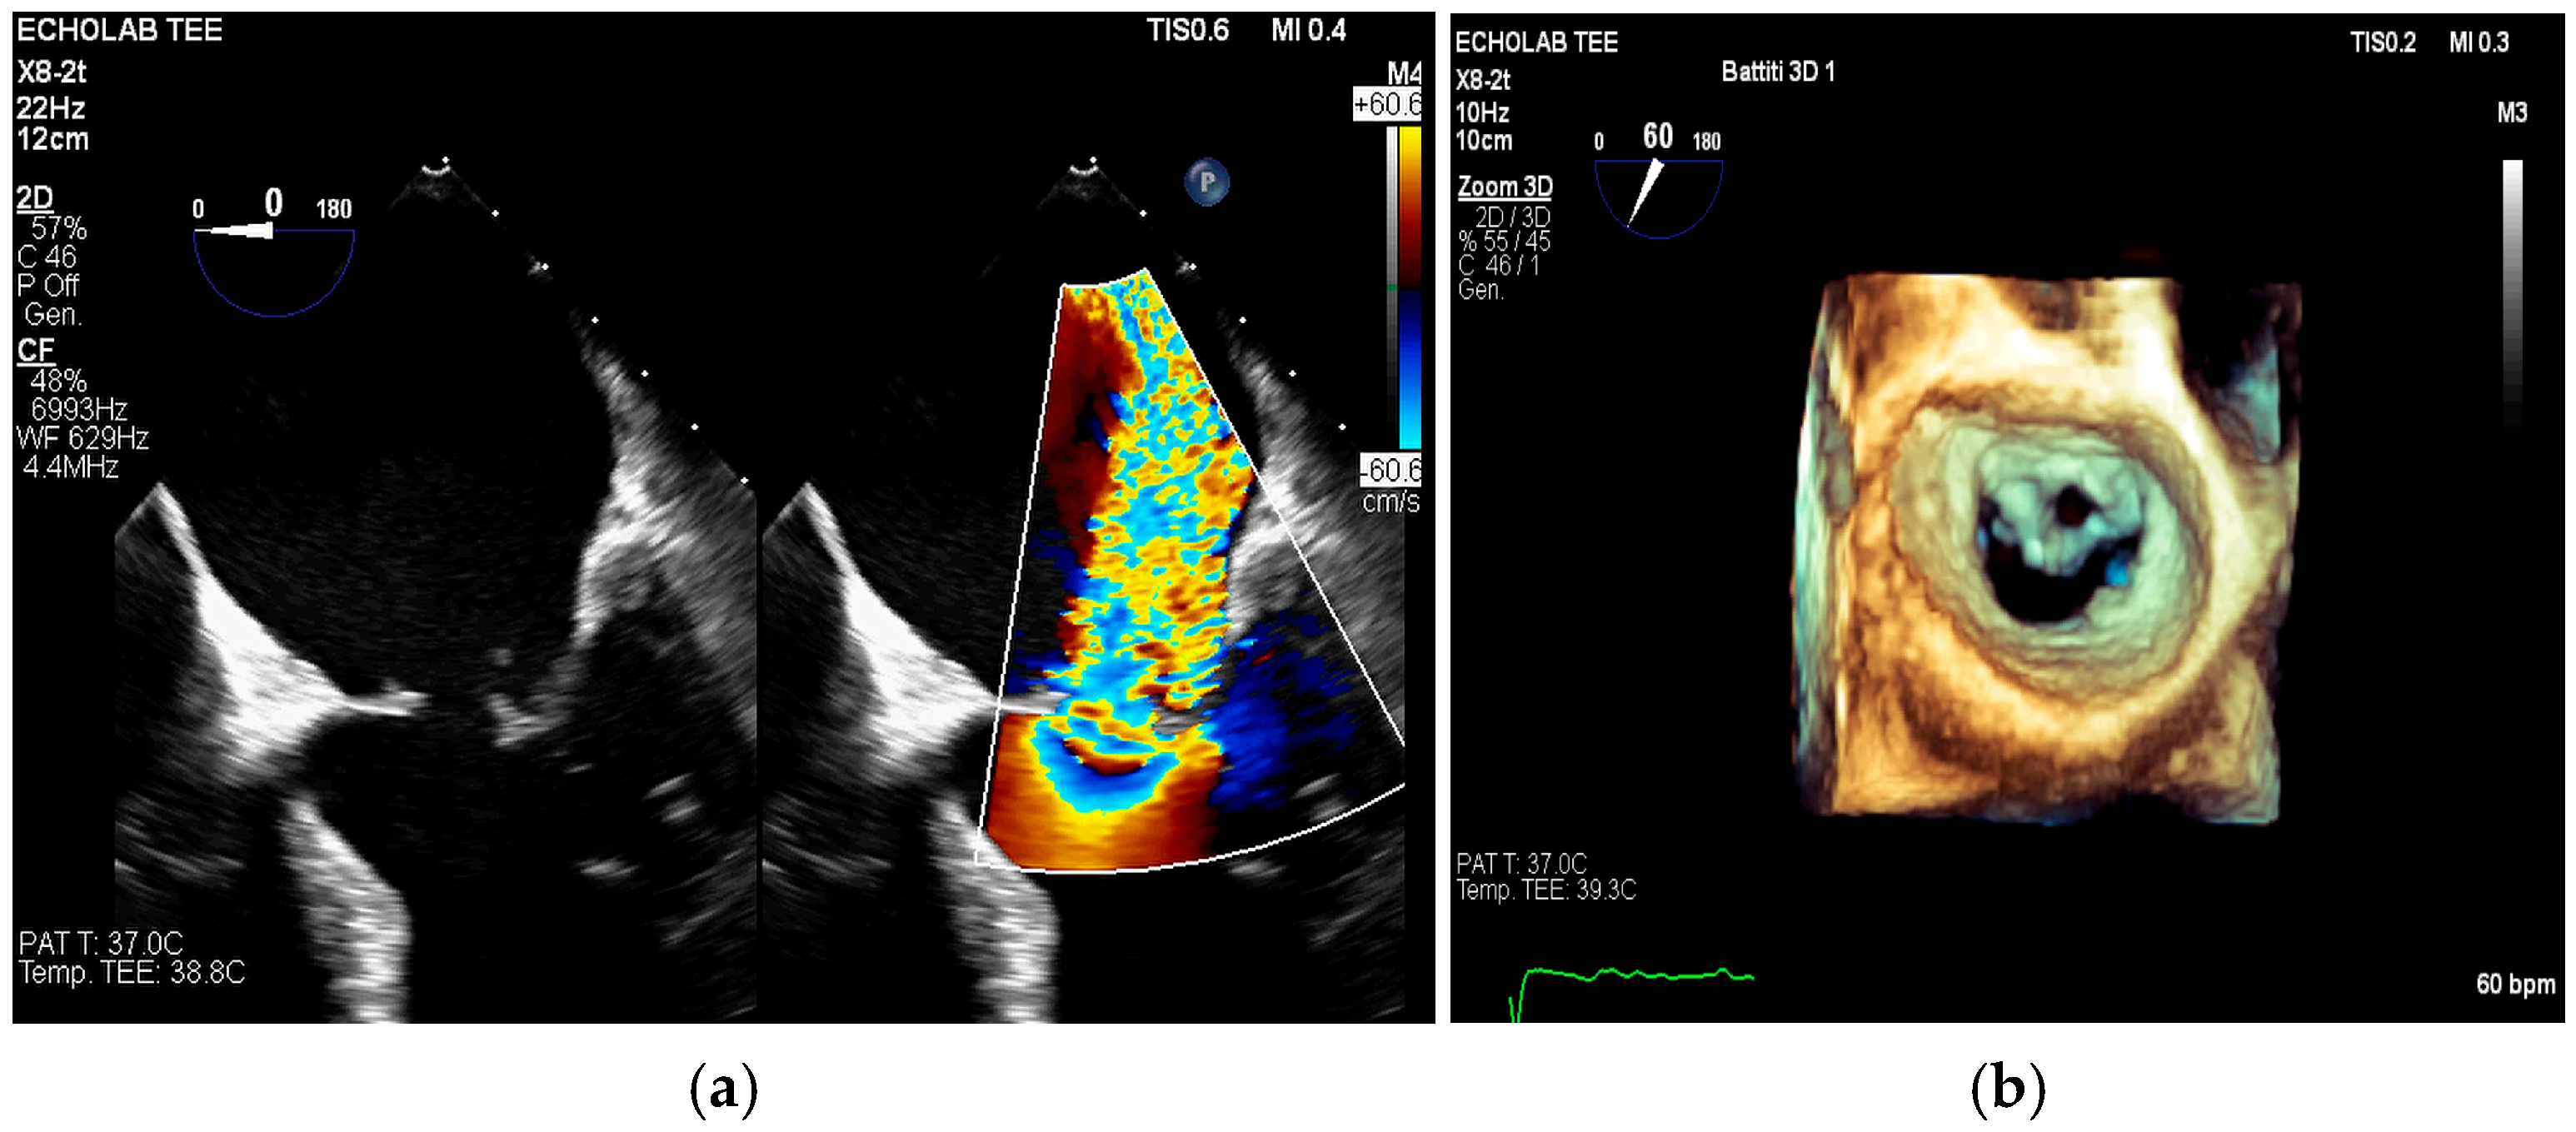

4. Echocardiography

- valvular or leaflet perforation, i.e., tissue defects causing valvular regurgitation originating from the site of perforation.

- valvular aneurysm, a saccular outpouching of a valve leaflet, protruding into the atrium or ventricle.

- perivalvular or perigraft abscess, an echolucent or echodense area adjacent to the valve annulus or prosthetic ring often with irregular borders and sometimes with evidence of cavity formation.

- pseudoaneurysm, a contrast-filled outpouching with a narrow neck communicating with the cardiac lumen, often adjacent to the valve annulus. On echocardiography, it appears as a pulsatile cavity with systolic expansion and diastolic collapse.

- intracardiac fistula, visualized as an abnormal communication between cardiac chambers or vessels, is often detected by using color Doppler.

- significant new valvular regurgitation compared with previous imaging, i.e., increase in regurgitant jet size, vena contracta width…

- Echocardiography: As the cornerstone of diagnosis, echocardiography’s limitations in the setting of prosthetic material and operator dependence are well-known. The presence of sewing ring and stent frame shadowing can obscure critical findings, and Doppler flow malalignment may lead to underestimation of prosthetic valve gradients and regurgitation severity [37,58].